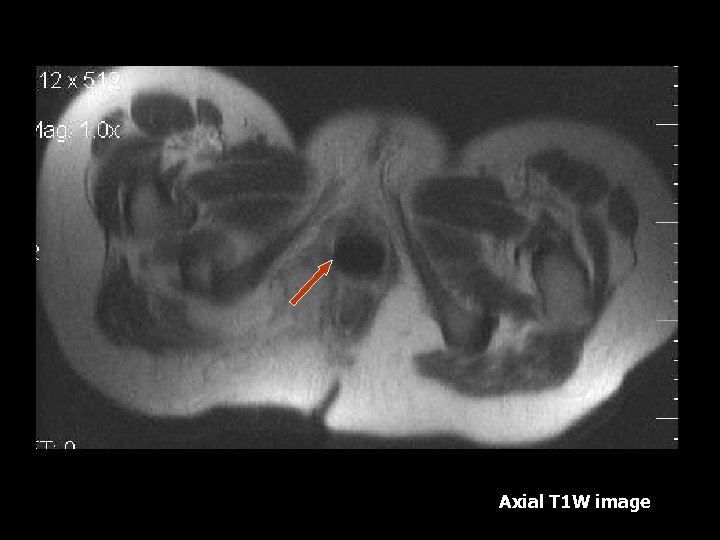

Axial FSE T 2 W image Axial T 1 W image Right ovarian cystic lesion bright on T 1 and T 2 -weighted images.

Axial STIR Axial T 2 W FSE image with frequency selective fat suppression Lesion intesity is supressed on STIR but not on frequency selected fat supression image consistent with hemorrhagic content

Hemorrhagic Cyst • Hemorrhagic cysts have typical appearance of blood products on T 1 W and T 2 W images(7). • T 1 weighted images will demonstrate low intensity due to subacute blood(7). • T 2 weighted images will demonstrate high signal(7). • Fat suppressed images • As the cyst ages, a hemosiderin rim will have low signal intensity on all sequesnces(7).